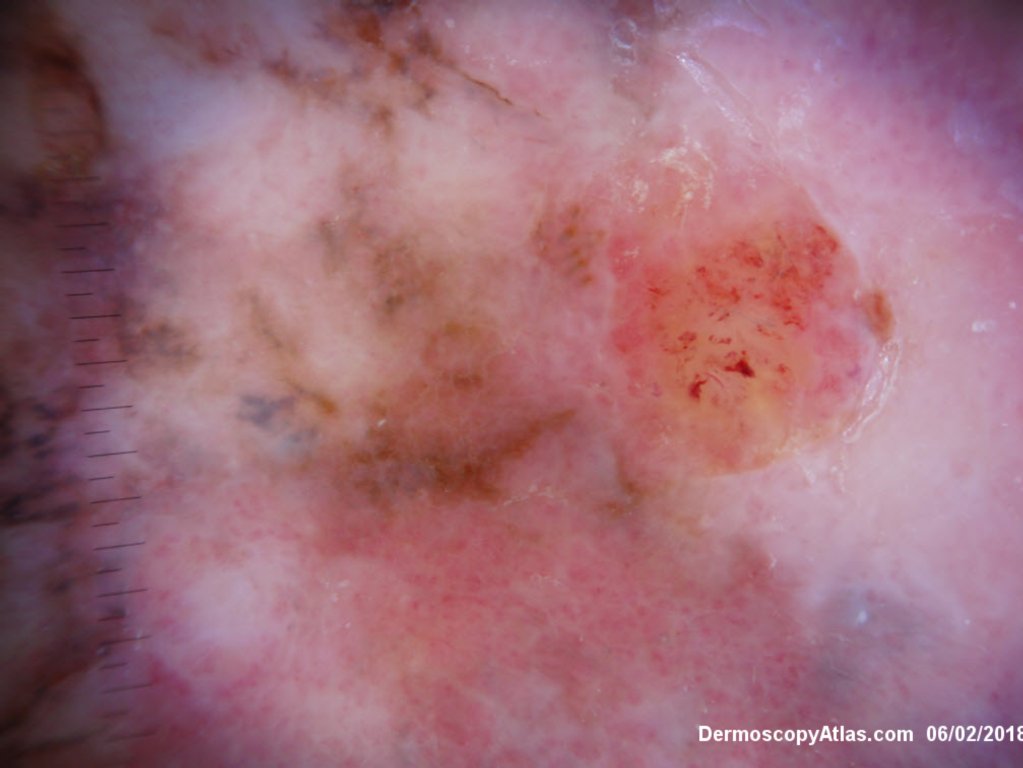

Description: Multiple colours in this pigmented lesion on the lower leg. New pink area

Lady in her early 80s who presented with this lesion on her ankle. The pigmented area had been there for some time but the pink area was bleeding and new. Shave of surrounding area and a punch biopsy of the new pink area showed mainly surrounding in situ melanoma with invasive melanoma in the pink area 1.8 mm thick. Having a 2cms margin excision of the whole area and a graft.